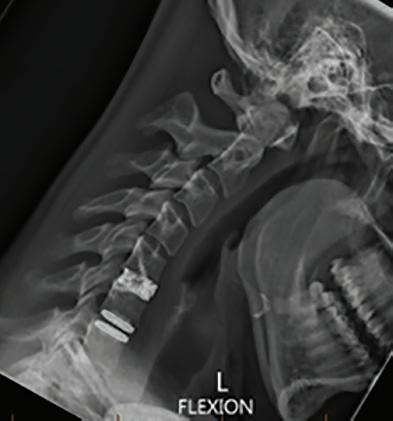

Cystic fibrosis is a complex, multisystem condition caused by one of several genetic alterations that can be passed down through family bloodlines or occur spontaneously. The mutations affect the CFTR gene, which manages the flow of water and chloride in and out of cells lining many of the body’s soft organs, including the respiratory, digestive and reproductive tracts.

The result is a build-up of sticky mucus, leading to recurrent respiratory infections, difficulties absorbing nutrients from food, damage to the pancreas and an increased risk of diabetes, and fertility problems.

Modulator therapies are considered the biggest change in the CF world in more than 50 years, after years of only small incremental improvements. Although not a cure, they have the potential to move CF from being a debilitating, chronic disease to something much more manageable.

In the past, the focus was largely on CF’s respiratory issues, as those

symptoms were the most obvious, but now the approach is more holistic and addresses other systems in the body, such as nutrition, cardiac care and endocrinology.

A few years ago Mr Messer was facing the prospect of needing a lung transplant when the drug Trikafta came along, which he credits for saving his life, giving him more energy and improving his lung function.

While he still needs treatment for chest infections, takes medication daily and his lungs are still damaged, the rate of it advancing has slowed.

“I know when I’m unwell now, but the symptoms are different to when I was unwell before I started the treatment, so it’s harder to recognise when you’re having an exacerbation,” he said.

“In the old days you would cough a lot more, and cough a lot more gunk up, but because the drugs are stopping that cycle, it sort of sneaks up on you – you start getting a bit tired and breathless and realise you’re actually unwell, so you’re sort of learning how to live in a new body.”